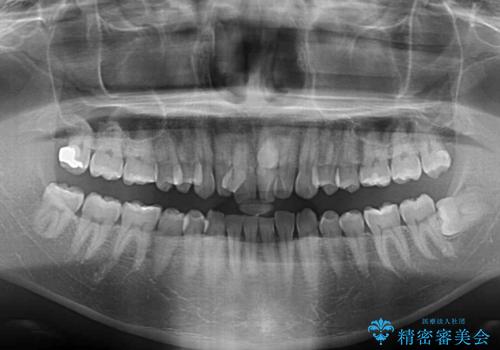

骨格的に上顎骨がやや前方にあり、それが原因で下顎前歯が隠れるほどのディープバイトになっている状態でした。

補助装置を用いて、上顎大臼歯を積極的に後方移動させながら、ディープバイトを改善していくこととしました。